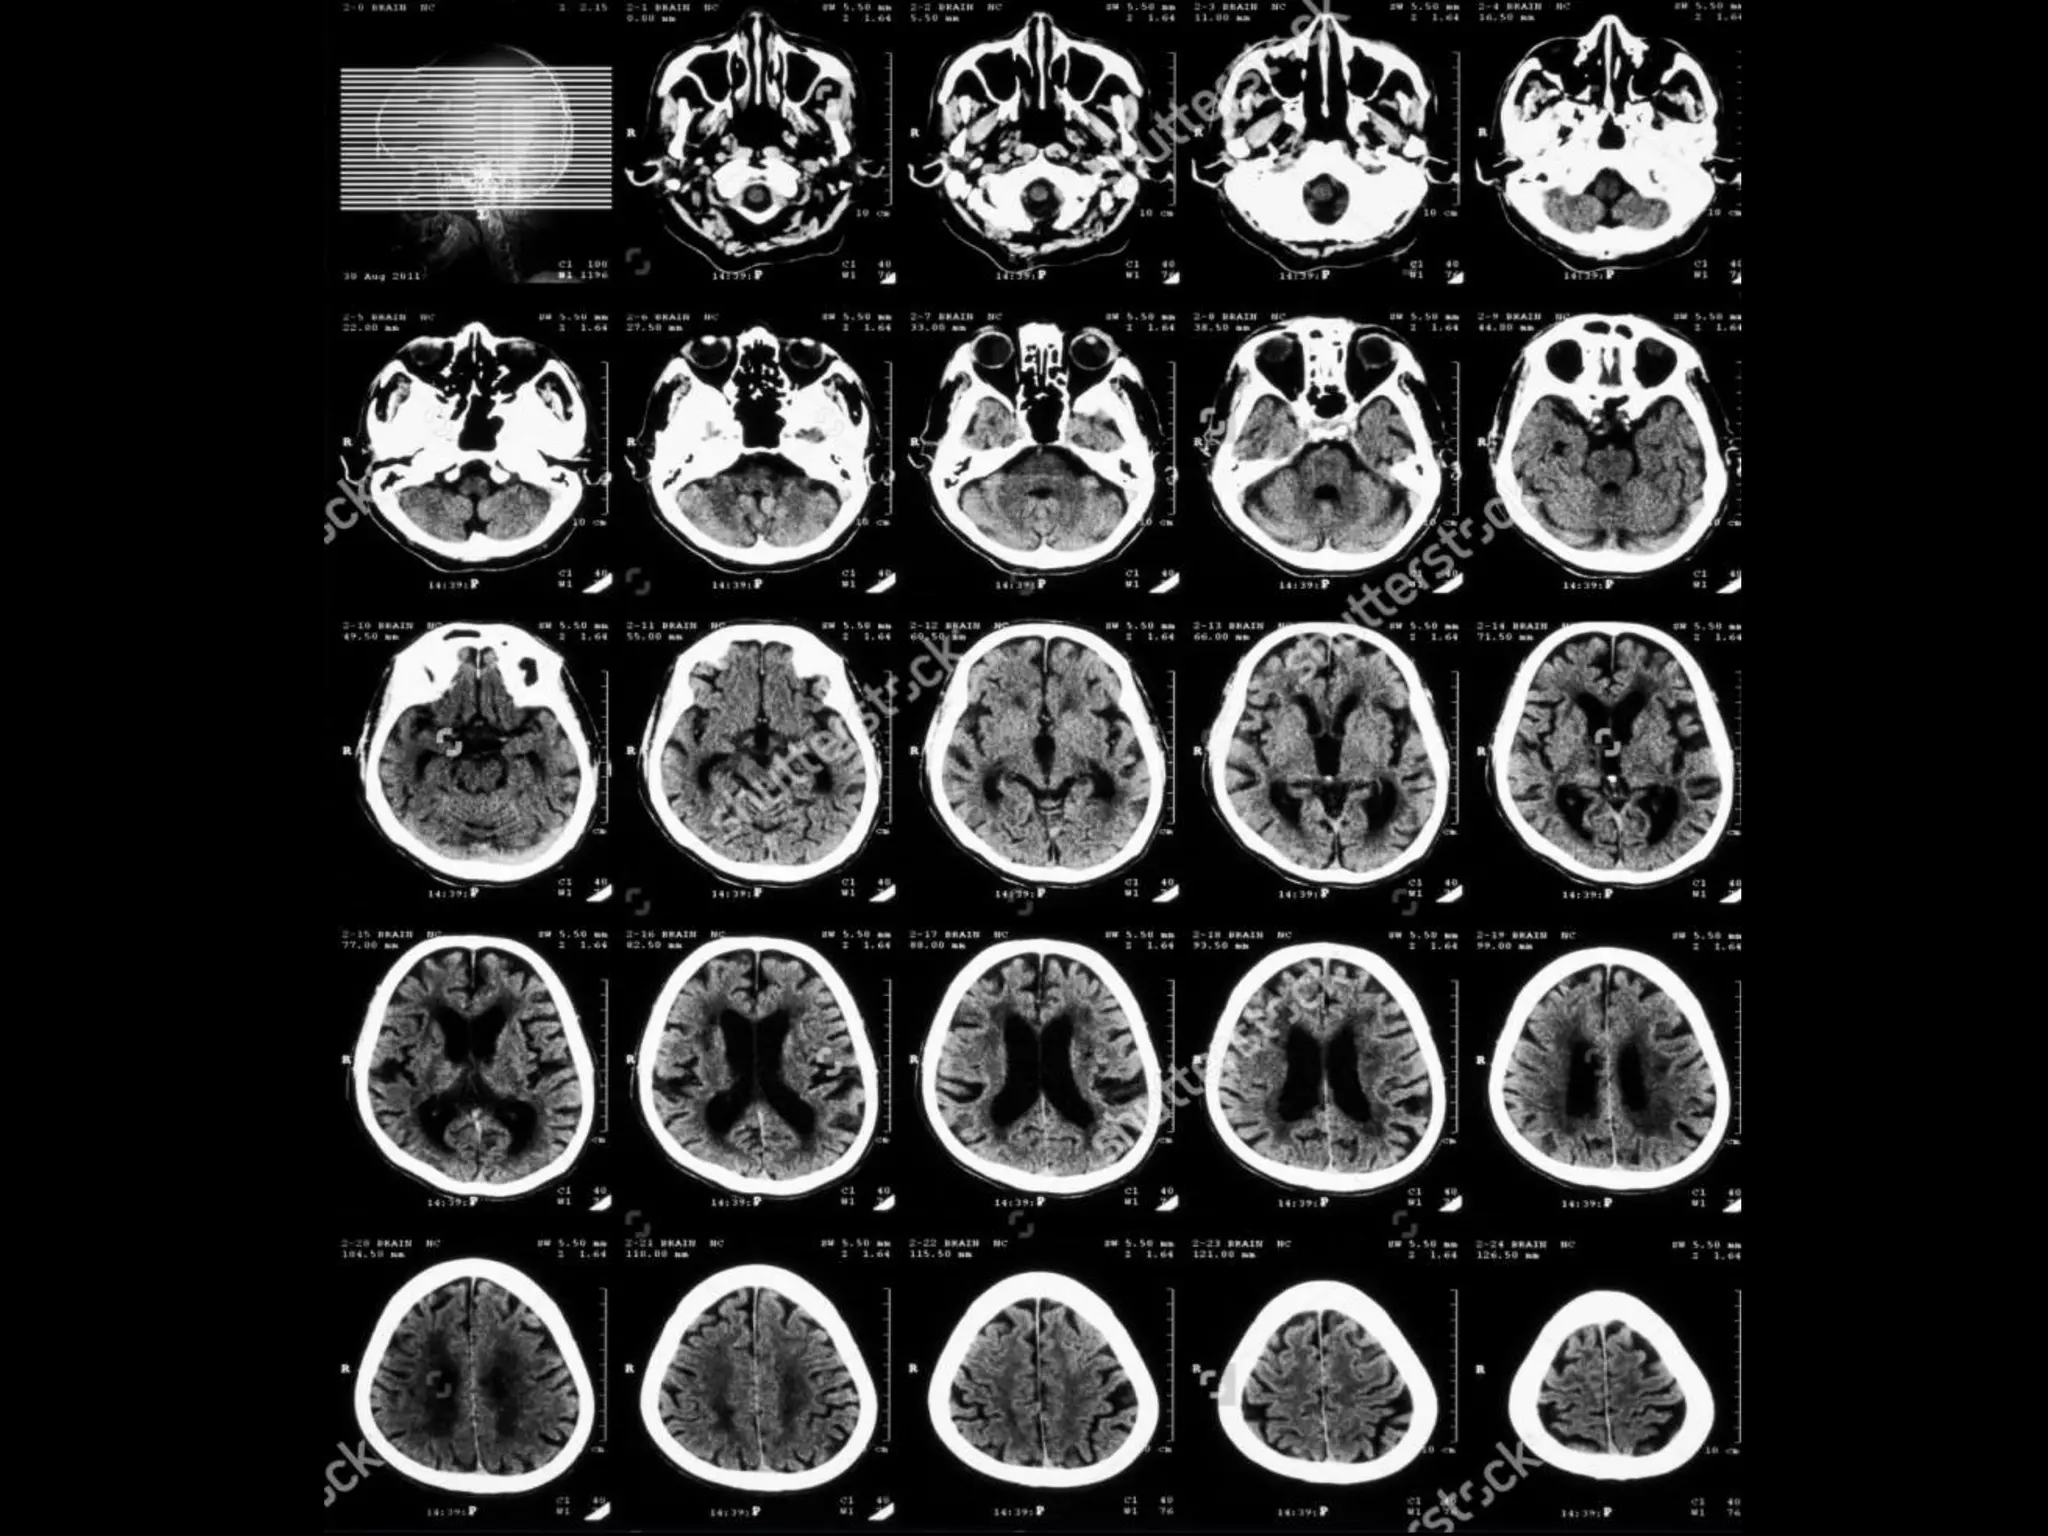

Giải phẫu cắt lớp sọ não

Axial !!!

Mp Virchow

đuôi mắt → ống tai ngoài

Thùy trán

Thùy đỉnh

Liềm đại não

Xoang TM

dọc trên

Não thất bên

Thùy chẩm

Đám rối mạch mạc

Sừng trước

Thùy đảo

Não thất ba

Bể trên tiểu não

Đầu nhân đuôi

Đồi thị

Nhân bèo

Bao trong

Bèo sẫm

Cầu nhạt

Cánh tay trước

Thùy thái dương

Tiểu não

Cầu não

Não thất tư

Bể trên yên

Khe Sylvius

Hành não

Xoang chũm

Giải phẫu

động mạch não